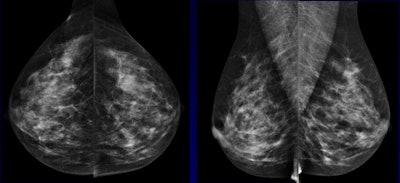

When it comes to screening women for breast cancer, those with dense breasts or tissue abnormalities tend to be the most troublesome, but breast ultrasound has proved, and continues to prove, its utility for these women, say leading researchers.

Estimates for mammography sensitivity range anywhere from 65% to 91%, and the masking effect of dense breast tissue is the most relevant cause of false negatives, according to Dr. Veronica Girardi from the Istituti Ospedalieri Bresciani in Brescia, Italy, a speaker at today's ECR 2015 refresher course.

"When we consider breast density, there are two different issues: One is that it's influencing cancer detection on mammographic imaging, and the second is its possible independent effect on breast cancer risk," she noted. "Breast density is significantly associated with an increased risk of breast cancer at any age, but it does not seem to influence ultrasound accuracy. For this reason, the association of ultrasound to mammography in women with dense breasts has been proposed by many authors, although there is no evidence of mortality reduction."